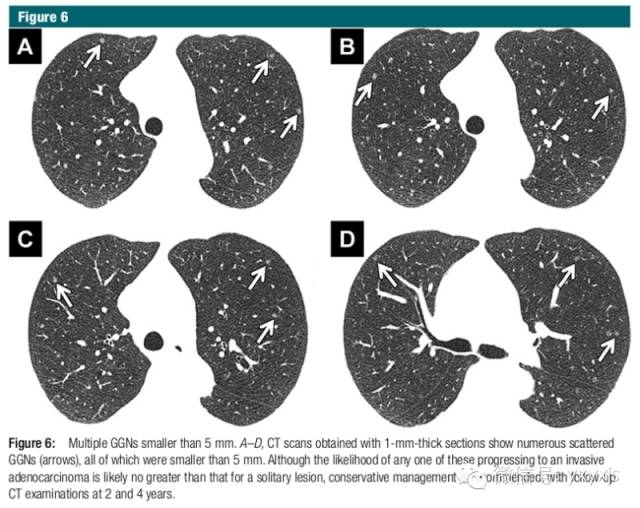

4 多发小于5mm的边缘清晰的GGO,应采取比较保守的方案,建议2年及4年后随诊。